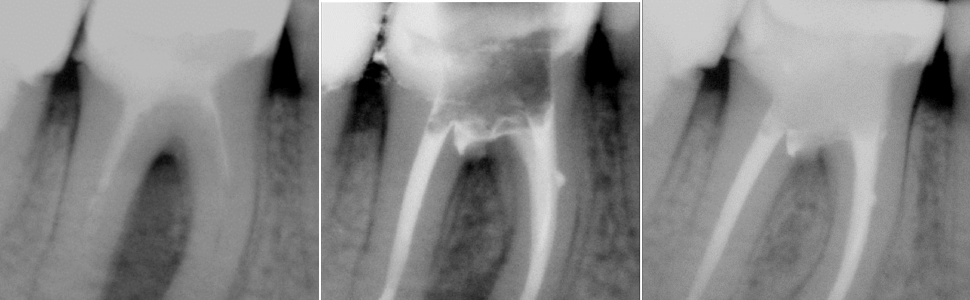

W pracy opisano postępowanie w przypadku zęba trzonowego żuchwy z jatrogenną perforacją dna komory. Ze względu na współistniejącą przewlekłą zmianę w tkankach okołokorzeniowych bezpośrednio po wypełnieniu perforacji materiałem bioaktywnym przystąpiono do antyseptycznego leczenia endodontycznego. Kontrola przeprowadzona po roku od zamknięcia perforacji i po 9 miesiącach od wypełnienia kanałów wykazała wygojenie okołokorzeniowej zmiany.

The paper describes the treatment of a mandibular molar with iatrogenic perforation in the chamber fl oor. Due to the concomitant periradicular chronic inflammatory lesion, antiseptic endodontic treatment was started immediately after closing the perforation with bioactive material. The follow-up was performed one year after filling the perforation and nine months after the obturation of the root canals. Healing of the periradicular lesion was confirmed.